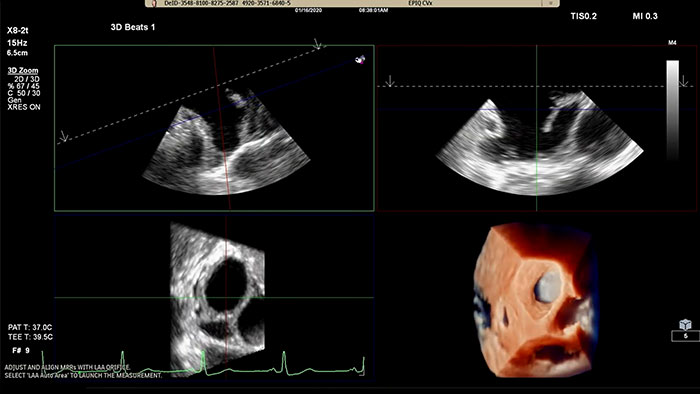

Assessing the left atrial appendage quickly, easily, intuitively.

The Philips LAA solution on EPIQ CVx.

Rapidly acquire LAA orifice measurements in both traditional rendering or in TrueVue Glass rendering, with 3D Auto LAA